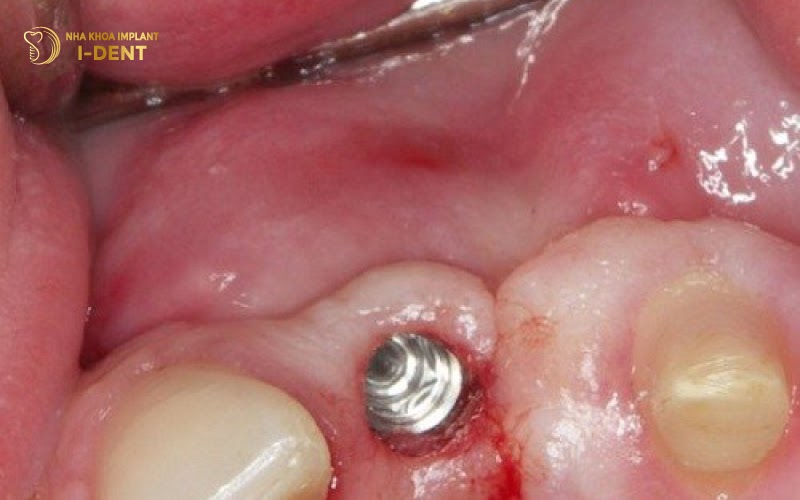

Biểu hiện của nhiễm trùng gồm sưng đau tăng dần, đỏ nóng vùng cấy ghép, có mủ hoặc dịch tiết, mùi hôi từ vùng implant và có thể kèm sốt. Nếu không được điều trị kịp thời, nhiễm trùng có thể lan rộng gây tiêu xương hàm, thất bại implant hoàn toàn, implant đào thải hoặc nhiễm trùng máu.

Nhiễm trùng vùng cấy ghép implant thường có biểu hiện xưng đỏ hoặc có dịch mủ tại vị trí cấy implant.